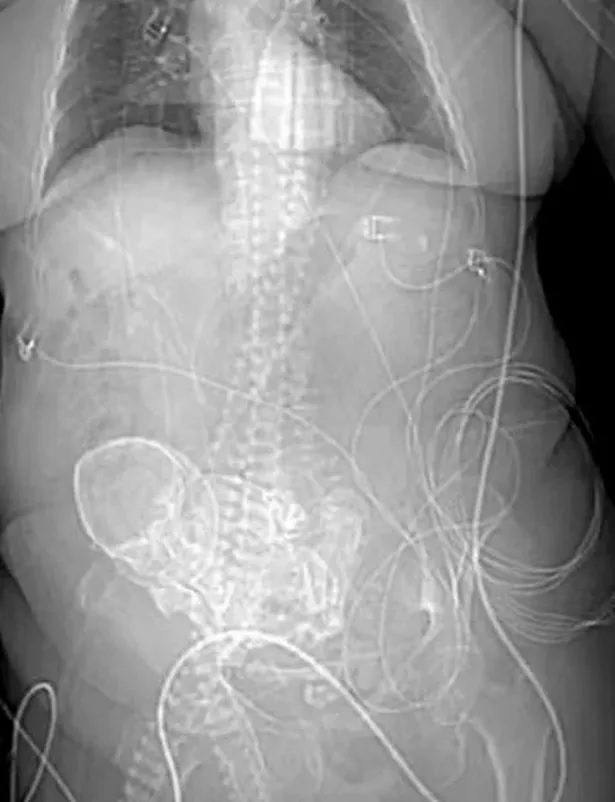

Eventually, she went to the hospital and a 3D tomography scan revealed the hidden “stone baby", dating back to her last pregnancy.

This unusual condition, known as a lithopedion, happens when

a foetus dies but can't be absorbed by the mother's body. Instead, it stays in

the abdominal cavity, forming a calcium shell around it.

Before this shocking discovery, doctors thought she might

have had cancer.

When the stone baby was discovered, Daniela, from an indigenous tribe near Brazil's border with Paraguay, had an operation on March 14.